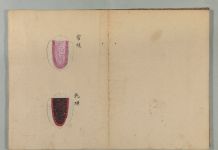

舌質正常・苔薄白・脈弦。

舌質淡・舌苔少・脈沈弱。

舌淡・脈弱無力。